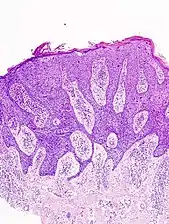

In situ disease

Bowen's disease is essentially equivalent to and used interchangeably with cSCC in situ, when not having invaded through the basement membrane.[12] Depending on source, it is classified as precancerous[13] or cSCC in situ (technically cancerous but non-invasive).[47][48] In cSCC in situ (Bowen's disease), atypical squamous cells proliferate through the whole thickness of the epidermis.[12] The entire tumor is confined to the epidermis and does not invade into the dermis.[12] The cells are often highly atypical under the microscope, and may in fact look more unusual than the cells of some invasive squamous-cell carcinomas.[12]

cSCC in situ, high magnification, demonstrating an intact basement membrane.[12]